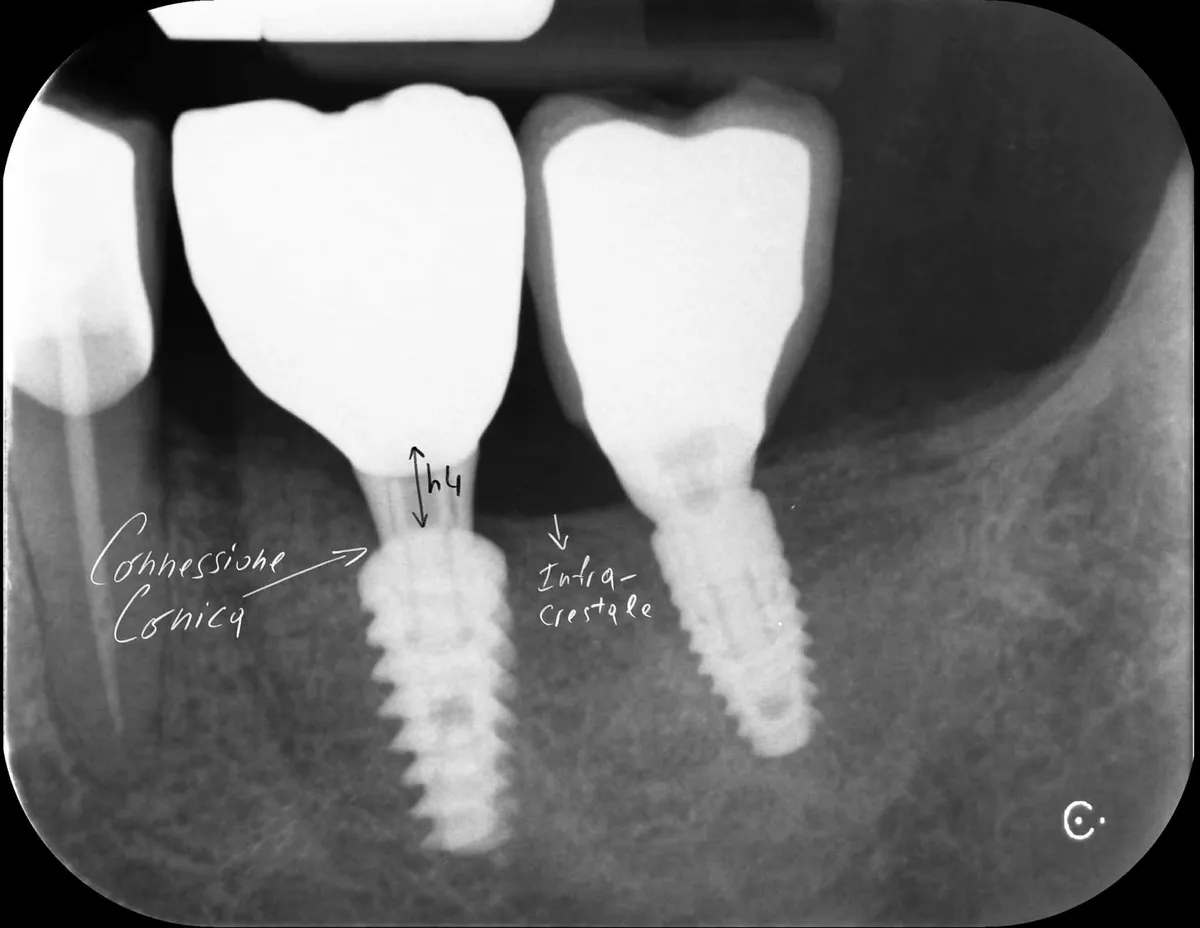

Caso clinico: espansione crestale ERE con impianto immediato e rigenerazione simultanea. Da ponte fallito a impianto in un'unica seduta.